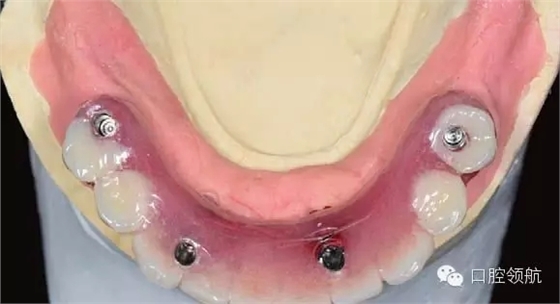

手術(shù)當天取模,當天灌注石膏模型,上牙合架,開始準備制作螺絲固定的過渡義齒(圖6-11,圖6-12)。

圖6-11 安放閉口轉(zhuǎn)移桿后的牙合面照